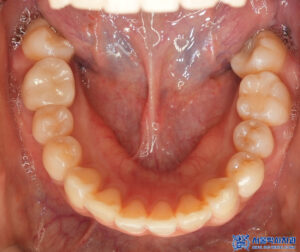

육안으로 확인해 보았을 때,

충치가 꽤나 진행되어

깊어 보이는 치아들이 많았습니다.

마무리 후 사진입니다.